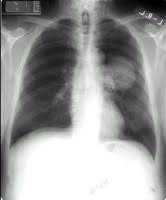

What Are The First Signs Of Small Cell Lung Cancer : Metastatic Non Small Cell Lung Cancer Esmo Clinical Practice Guidelines For Diagnosis Treatment And Follow Up Annals Of Oncology - The early symptoms of lung cancer may be a slight cough or shortness of breath, depending on which part of the lung is affected.. Small cell lung cancer is a disease in which malignant (cancer) cells form in the tissues of the lung. Chronic cough that doesn't go away or worsens. Small cell lung cancer (sclc) is one of the two major types of lung cancer. The early symptoms of lung cancer may be a slight cough or shortness of breath, depending on which part of the lung is affected. Named initially for how the cancer cells look under the microscope, these two types account for most of the 230,000 newly diagnosed cases of lung cancer in the u.s.

Signs and symptoms of lung cancer typically occur when the disease is advanced. Signs and symptoms of small cell lung cancer include coughing and shortness of breath. Cough that remains unrelieved and gets worse over time hemoptysis (coughing up blood) or reddish spit Signs and symptoms of lung cancer may include: Small cell carcinoma (oat cell cancer) combined small cell carcinoma.

Signs and symptoms of lung cancer may include: As the cancer develops, these symptoms may become more severe or intense. Specific findings depend on numerous factors including the exact location and size of the tumor, the extent of invasion of the tumor into nearby tissue or organs, and whether the disease has remained localized or spread to other areas of the body (metastasized). The most common cause of lung cancer is tobacco smoking, which is estimated to be responsible for about 90% of cases of the disease. There are two main types of small cell lung cancer. After a cancer diagnosis, staging provides important information about the extent of cancer in the body and anticipated response to treatment. These abnormal cells kill the normal cells of the body and disrupt the normal body functions. Named initially for how the cancer cells look under the microscope, these two types account for most of the 230,000 newly diagnosed cases of lung cancer in the u.s. Cancer anywhere in the body can cause a person to feel unwell in a general way. Signs and symptoms of lung cancer typically occur when the disease is advanced. Like many other types of cancer, lung cancer may also cause systemic symptoms, like loss of appetite or general fatigue. When cells of the lung start to undergo a degenerative transformation in appearance and start growing rapidly in an uncontrolled manner, the condition is called lung cancer. Swelling of the neck or face